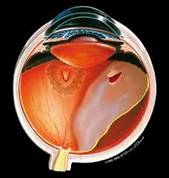

5.Retinal Detachment

If the retina gets separated from underlying layers, the condition is known as retinal detachment. the patient complains of flashes of light in front of eye, floaters and sudden decrease of vision or sensation of curtain coming from one side. Treatment is by surgery. In fresh and uncomplicated cases conventional retinal detachment surgery suffices. But in complicated and advanced cases vitreoretinal surgery and silicon oil injection etc is required.

Retinal Detachment